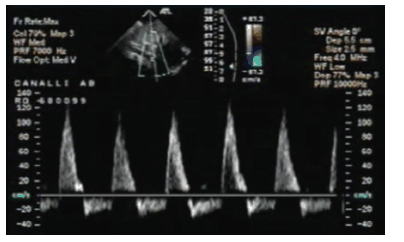

Você foi chamado para avaliar um RN na maternidade. O mesmo encontra-se dispneico e com dificuldade para mamar. Avaliando as imagens do ecocardiograma transtorácico realizado no dia anterior você encontra a imagem abaixo.

Um provável diagnóstico desse RN é: